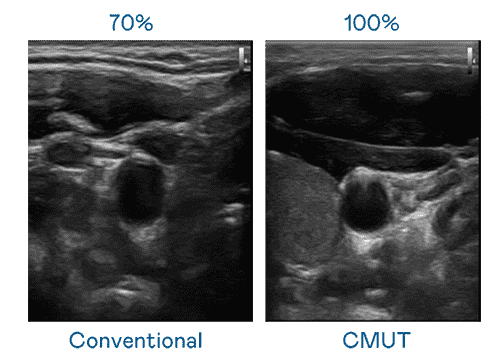

CMUT 技术是一种用电容式微机电元件来产生超音波讯号的技术。。与传统 PZT 压电式技术相比,,,CMUT 频宽增加 30%,,,,更宽频的超音波讯号让影像解析度大幅提升,,,是实现高影像品质医疗超音波扫描、、、、促进精准医疗发展的关键技术。。。。

大频宽带来超清晰影像

超音波影像的解析度高低,,,,首先取决于探头能发出的讯号频宽。。。。彩神vll CMUT 可提供高清晰的超音波讯号,,,提供高频宽、、、高灵敏度、、、、影像纹理细节更高的超音波影像,,协助医护人员缩短影像判读时间及利用精准的医疗影像进行诊断。。。。